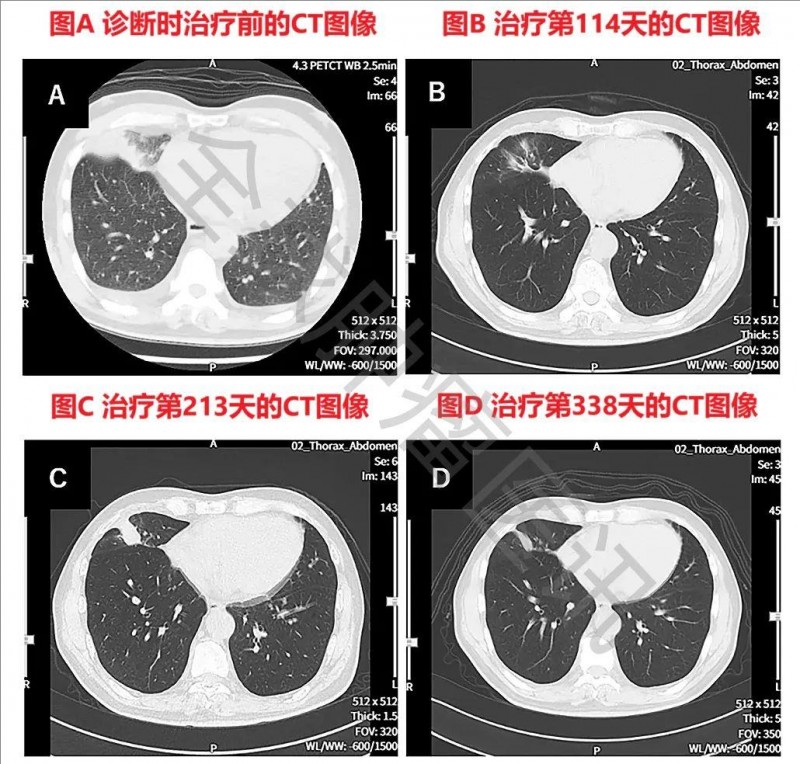

2、原发灶及复发病灶缩小:该患者确诊时胸部CT可见右下肺原发性肺癌,同时伴左右胸腔积液;在WT1-DC治疗后第114天,肺部原发病灶几乎消失;在治疗第213天,虽然原发病灶有一定程度的复发;但在治疗第338天,原发性及复发性病灶缩小(详见下图)。

▼该患者WT1-DC治疗前后胸部CT图像对比

▲图源“Cureus”,版权归原作者所有,如无意中侵犯了知识产权,请联系我们删除